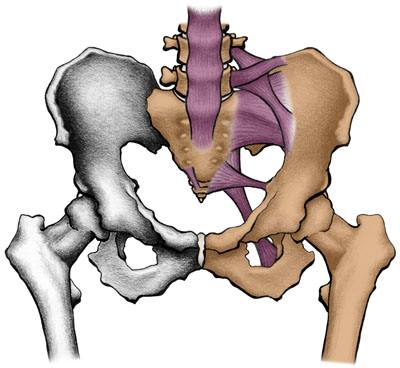

广州强直葆髋医院专家指出:作为常见的骨科顽疾,股骨头堵塞的血管是…… 【详情】

髋关节疼痛关节僵硬与活动受限病情反复,治疗效果差临床数据显示,股…… 【详情】